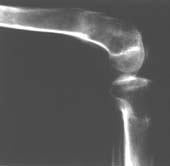

Пациент В. 53 лет, травма в феврале 2009. ДЗ. Открытый оскольчатый перелом нижней трети голени. При боли поступлении выполено ПХО, аппарат Илизарова. В последующем проводили ВХО, резекция костных отломков, укорочение 6 см, рана зажила. Была выполнена остеотомия большеберцовой кости в проксимальном отделе, резекция. Производилось тракция. На последних рентгенограммах выявлено, что одновременно с "выращиванием" регенерата произошло низведение надколенника на длину выращенного регенерата. Клинически: активное разгибание сохранено, объем движений в колене 180-110 градусов. Черными стрелками обозначен верхний край надколенника с одной и с другой стороны. Красная стрелка обозначает пальпируемую связку надколенника. Причина - остеотомия выше места прикрепления связки надколенника. Вопрос: была ли у кого подобная ситуация? Что делать? При первом обдумывании приходит решение: отсечение места прикрепления связки надколенника с костным блоком, перемещение на "правильное" место, укорочение сухожилия четырехглавой мышцы.